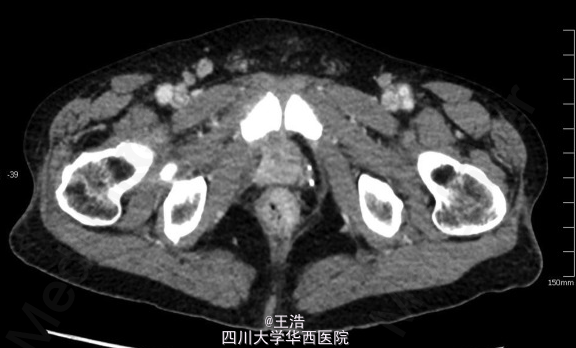

患者术后随访20个月。胸膝卧位检查,可触及距肛门约2.5cm一菜花样新生物。盆腔MRI可见直肠壁增厚,在前列腺与输尿管底部之间可见一肿块。盆腔CT未见淋巴结受累,腹部胸部CT也正常。初步诊断为直肠癌。